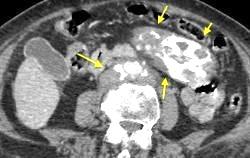

Ganglios retroperitoneales (flechas negras)

germinales del testículo izquierdo Nódulos pulmonares múltiples. (flechas verdes). Ganglios paratraqueales. (flechas amarillas). Dudoso ensanchamiento retrocrural (flechas negras)

Panda A et al. “Straddling Across Boundaries”. Thoracoabdominal Lesions: Spectrum and Pattern Approach. Curr Probl Diagn Radiol, 2015